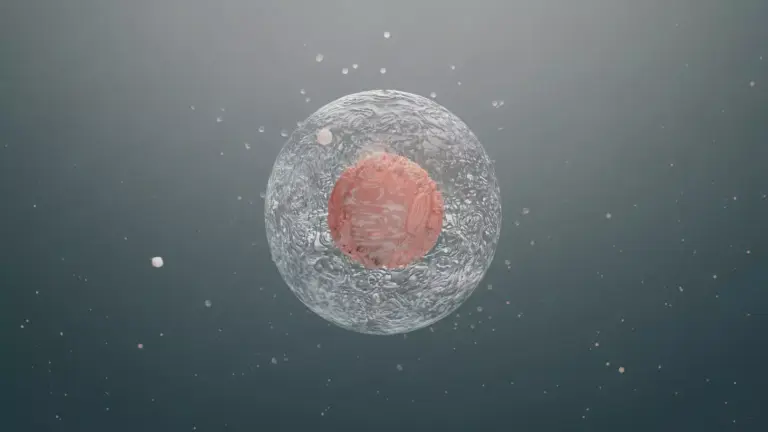

Peripheral Neuropathy

Peripheral neuropathy damages or messes with peripheral nerves. This can lead to left side leg pain or pain on the right side, depending on the nerves. It can happen due to diabetes, poor nutrition, or other reasons.

To manage it, we treat the cause and ease symptoms. This includes medication and making lifestyle changes.

Vascular Causes of Leg Pain

Leg pain can come from different vascular causes. It’s important to know these causes for proper treatment. Vascular issues can really affect your life, so understanding them is key.

Deep Vein Thrombosis (DVT)

Deep Vein Thrombosis is when a blood clot forms in deep veins, usually in the legs. You might feel pain, swelling, and redness in the leg. If the clot moves to the lungs, it’s a serious problem called a pulmonary embolism.

Things that increase your risk include sitting for a long time, having surgery, or having a family history of DVT.